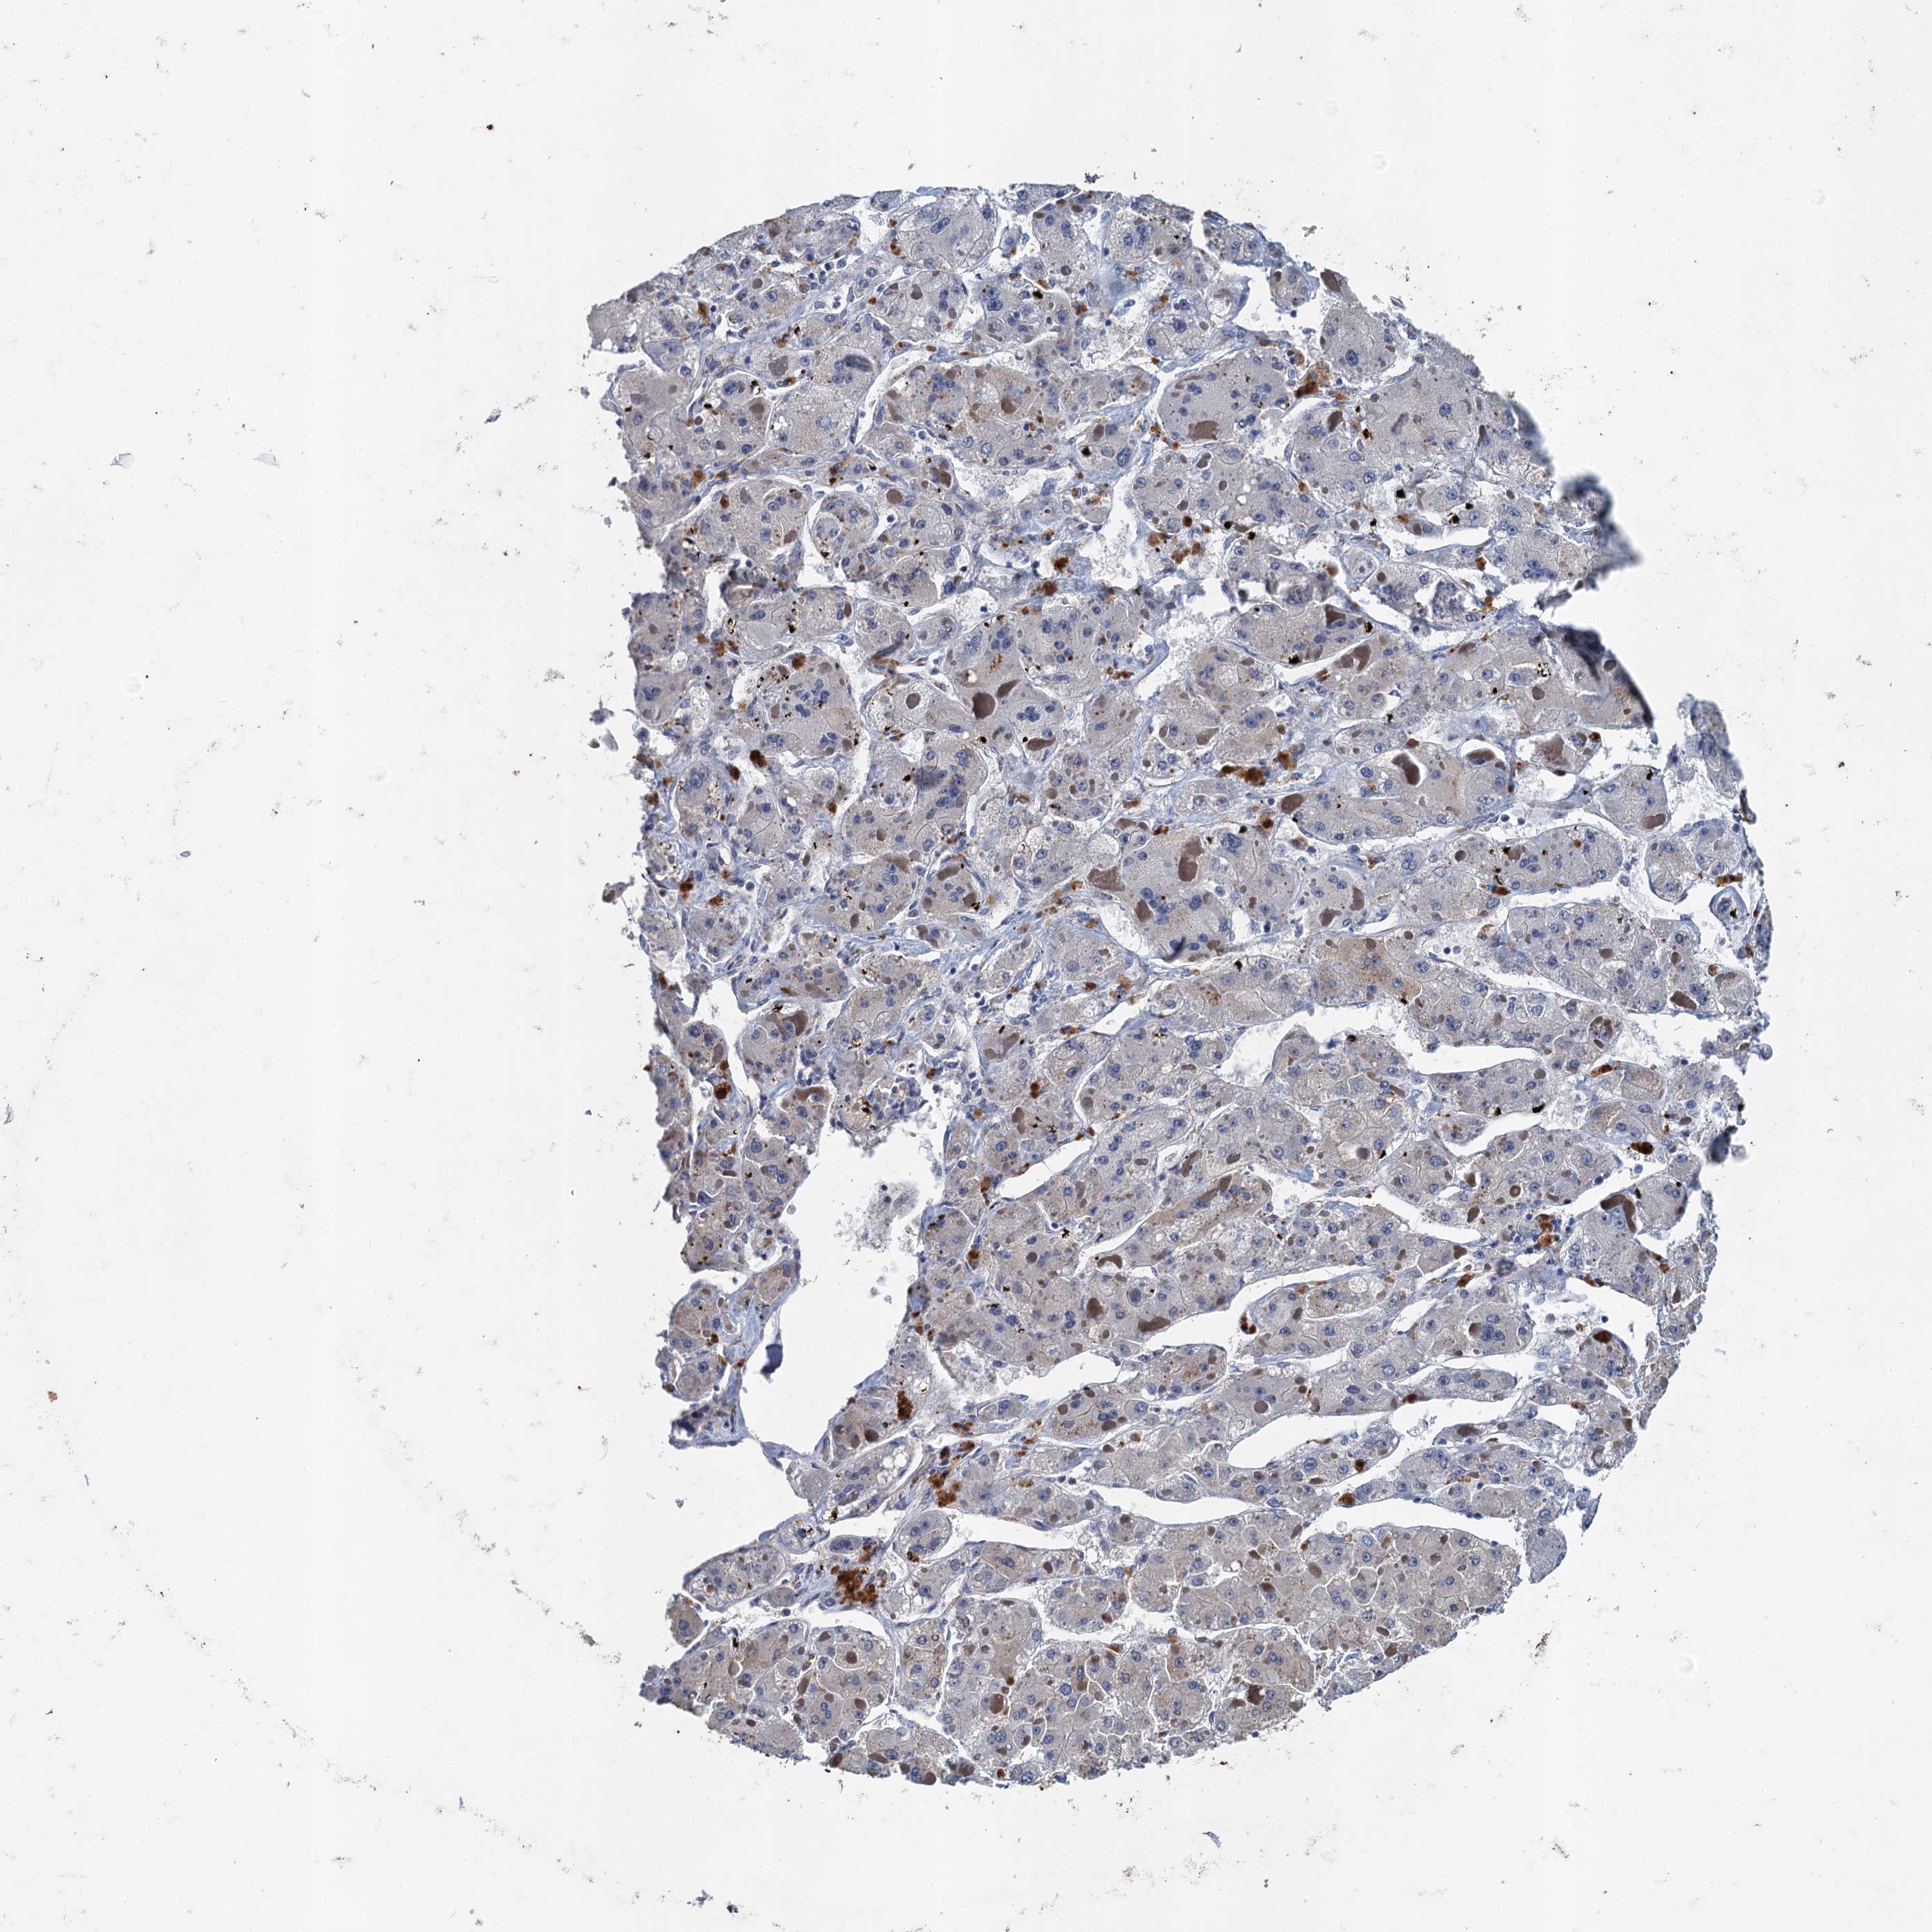

LIVER CANCER - Protein expressioni

A mouse-over function shows sample information and annotation data. Click on an image to view it in a full screen mode. Samples can be filtered based on level of antibody staining by selecting one or several of the following categories: high, medium, low and not detected. The assay and annotation is described here.

Note that samples used for immunohistochemistry by the Human Protein Atlas do not correspond to samples in the TCGA dataset.

Antibody stainingi

Antibody staining in the annotated cell types in the current human tissue is reported as not detected, low, medium, or high, based on conventional immunohistochemistry profiling in selected tissues. This score is based on the combination of the staining intensity and fraction of stained cells.

Each image is clickable and will lead to virtual microscopy that enables deeper exploration of all samples and also displays staining intensity scores, fraction scores and subcellular localization as well as patient and tissue information for each sample.

Antibody HPA039730

Antibody HPA040385

Staining

High

Medium

Low

Not detected

Intensity

Strong

Moderate

Weak

Negative

Quantity

>75%

75%-25%

<25%

None

Location

Nuclear

Cytoplasmic/membranous

Cytoplasmic/membranous,nuclear

Cholangiocarcinoma

Carcinoma, Hepatocellular, NOS